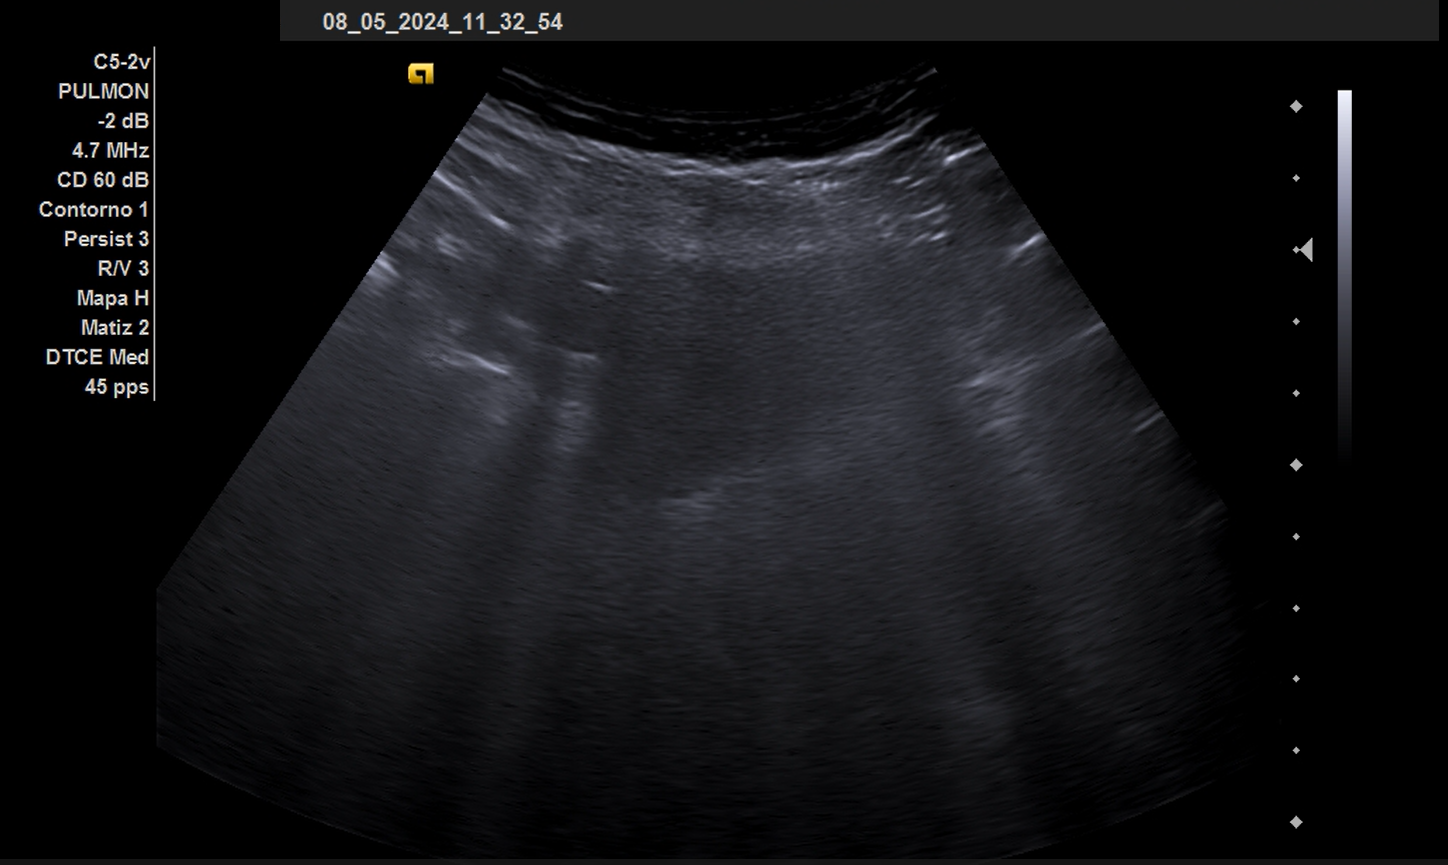

La ecografía pulmonar se ha realizado en el seguimiento.

El abordaje clínico es la base de la atención al paciente. Como complemento a la exploración física se debe practicar una ecografía, en este caso pulmonar donde se visualizan Líneas E, que se inician desde piel a diferencia de las líneas B que se inician desde línea pleural. En el caso en cuestión la ecografía ha complementado el seguimiento desapareciendo dichos hallazgos al mes.